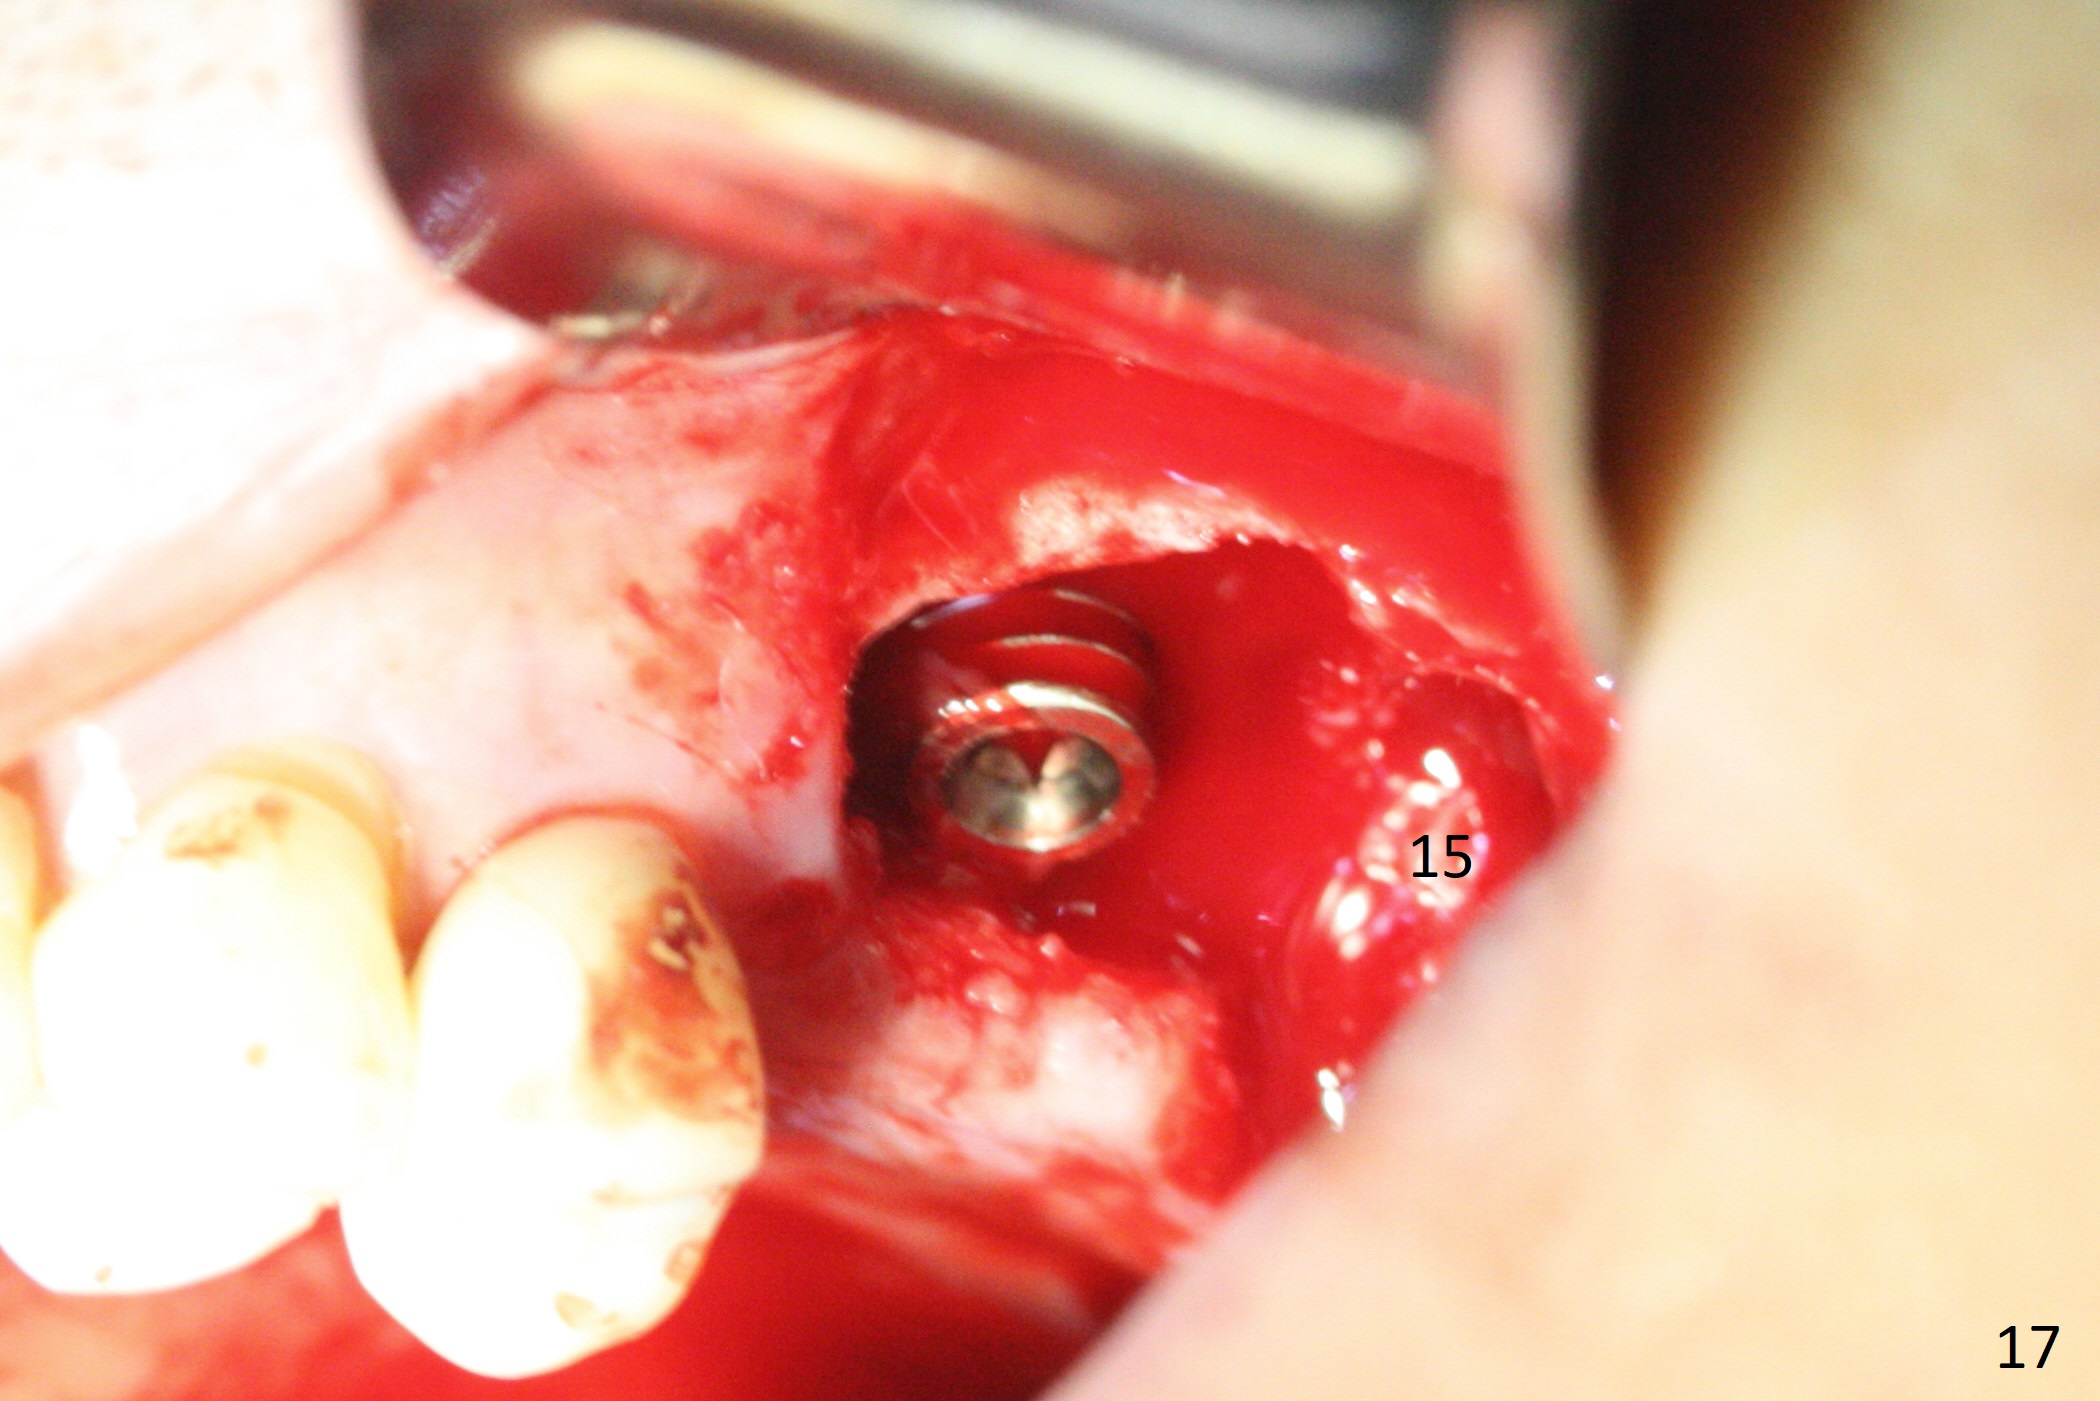

The amount of the bone graft mesial and distal the implant seems to reduce 3 and 4 months postop, respectively (Fig.6,7 arrowheads). When the acrylic is cut off 4 months postop, the bone graft is loose. The gingiva is unhealthy. The abutment and implant are loose. A healing abutment is placed (5x4 mm). The implant is torqued to 35 Ncm 6 months postop with the healing abutment reapplied. The patient will return for follow up nearly 9 months postop. A larger healing abutment will be used if the implant is stable. Two weeks later, use a smaller restorative abutment for easy impression. In fact the implant is unstable with #15 mesial shift due to abnormal occlusion with #17 (Fig.8). Bone density around the implant is low (* in Fig.9 (PA), 10,11 (CT sagittal, coronal sections)). A healing screw is placed for self healing. A 2nd option is to remove the implant (Fig.12), BEB (Fig.13) and place the implant deeper (Fig.14) or larger one (5.5-6.5x13 mm). The 3rd option is to place larger and longer implants (Fig.15 (tapered), 16 (cylindrical)). The implant access has partially closed 14 months postop, but there is a small buccal opening with sanguine exudate. Incision reveals severe bone loss around the implant; the mobile tooth #15 is extracted (Fig.17). After debridement and irrigation with normal saline, Vera Graft (Fig.18 *) and Collagen plug are placed with periodontal dressing.